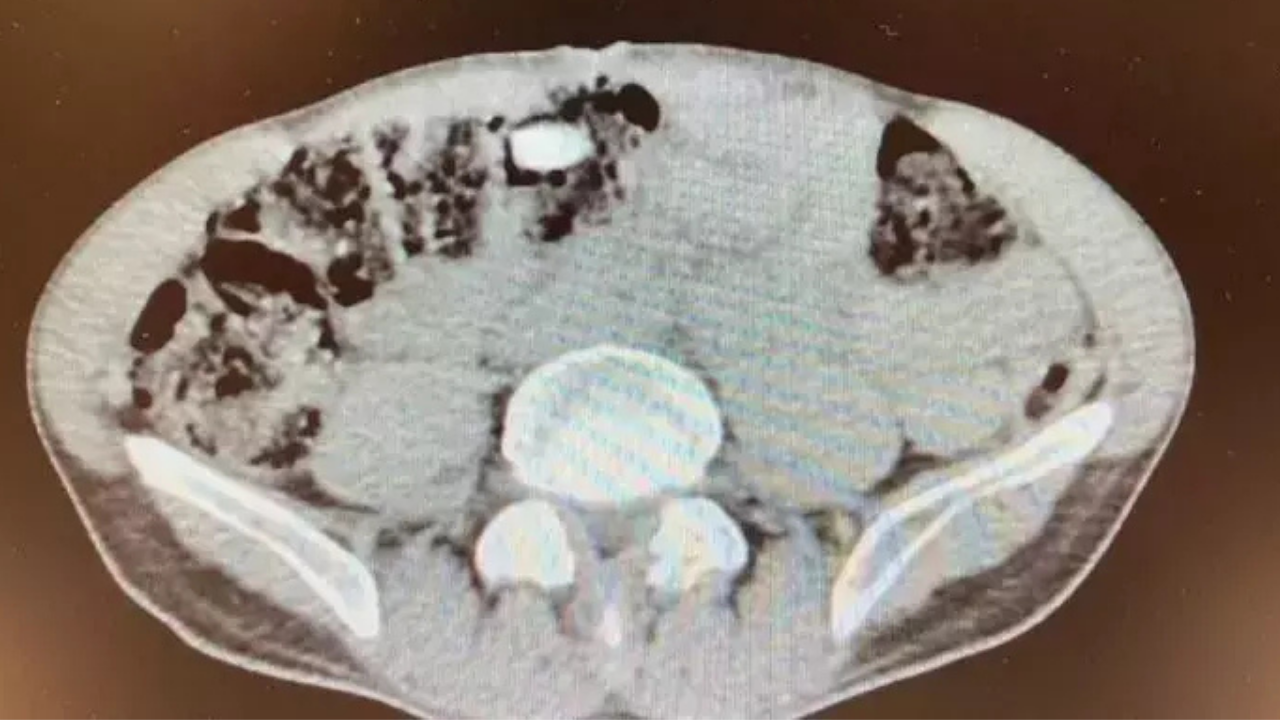

Hastanede röntgenle ortaya çıktı

İtiraf üzerine Denizli Devlet Hastanesi'ne götürülen zanlının iç beden muayenesinde, midesinde kapsül halinde uyuşturucu taşıdığı tespit edildi. Yapılan gözlem sonucunda şüphelinin midesinden 3 kapsül içinde 15 uyuşturucu hap çıkarıldı.